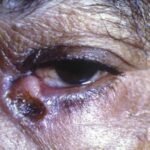

- Skin lesions are the most common manifestation of extrapulmonary disease. Cutaneous lesions favor exposed areas and enlarge over many weeks, from pimples that are minimally tender to well-circumscribed verrucous or ulcerative lesions, often with little inflammation. Verrucous lesions demonstrate raised irregular borders with crusting and purulent drainage, whereas ulcerative lesions are characterized by sharp and heaped-up borders with centrally located granulation tissue and exudate.

- Other unusual metastatic sites of infection include larynx, reticuloendothelial system (liver, spleen, lymph nodes, bone marrow), oropharynx, nose, and thyroid.